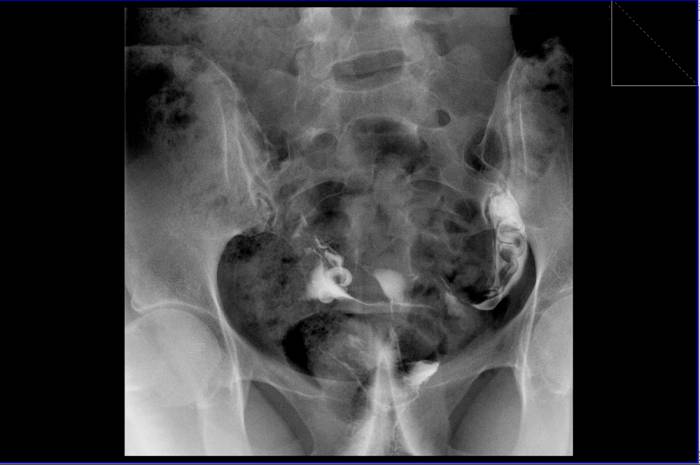

Правая и левая маточная труба проходят с трудом из-за наличия двустороннего клапанного сактосальпинкса.

На изображении четко видны расширенные и перекрученные маточные трубы.

Стрелкой слева показана маточная труба с наличием клапана сактосальпинкса.

Буква «R» на изображении указывает на правую сторону пациента.